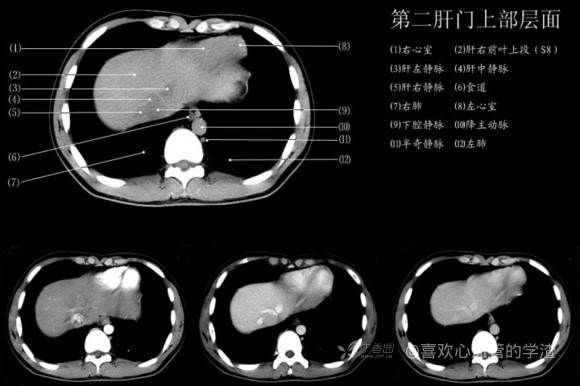

其实你离掌握上腹部 CT 影像只有一套高清实用图谱的距离,下面把我最喜欢的这本图谱分享给大家,为了方便阅读,我加了中文标识。后面附赠几张血管相对位置解剖关系图片,帮助大家理解(文中多图,建议在 wifi 环境下查看)。

在看 CT 断层的时候很多血管的走形关系一定要掌握,要不然会看的稀里糊涂,附赠几张上腹部血管关系走形图,帮助大家理解。比如这张,下腔静脉分出肝左静脉、肝中静脉、肝右静脉。